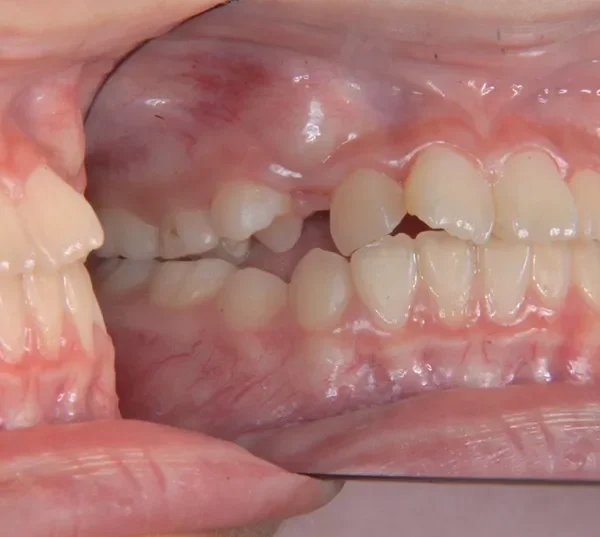

【子供の矯正(一期)】叢生・前歯がゆがんでいる・犬歯の生える隙間がない・9歳女児【M.O】

初診時年齢 小学校3年生 (女性) 主訴 前歯がゆがんでいる・犬歯の生える隙間がない

診断名 叢生 装置名

上下がガタガタで犬歯の生えるすきまがありません。

このままだと犬歯の生えるスペースがありません。放っておくと犬歯が上の位置からはえ、牙のようになってしまいます。

乳歯があるうちは上下オリジナル固定装置を利用し、永久歯が生えそろったらマルチブラケット装置を利用して治療しました。

初診